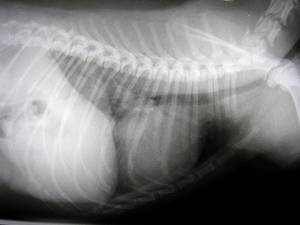

| Unsere Diagnosemöglichkeiten werden ergänzt durch das Röntgen. Somit können wir Krankheiten wie zum Beispiel die Hüftgelenks-Dysplasie (kurz HD) beim Hund aber auch Verletzungen wie z.B: Knochenbrüche feststellen. Aber auch bei der Diagnose von Herz-Lungen-Erkrankungen ist das Röntgen in der modernen Tierarztpraxis unverzichtbar. |